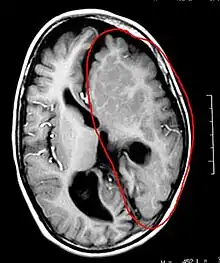

L'hémisphérectomie est une opération chirurgicale où un hémisphère cérébral (une moitié du cerveau) est enlevé ou déconnecté de l'autre hémisphère. Cette opération est utilisée pour traiter le syndrome de Rasmussen, et les enfants qui ont eu des accidents vasculaires cérébraux handicapants ou qui ont des crises d'épilepsie extrêmement fréquentes.